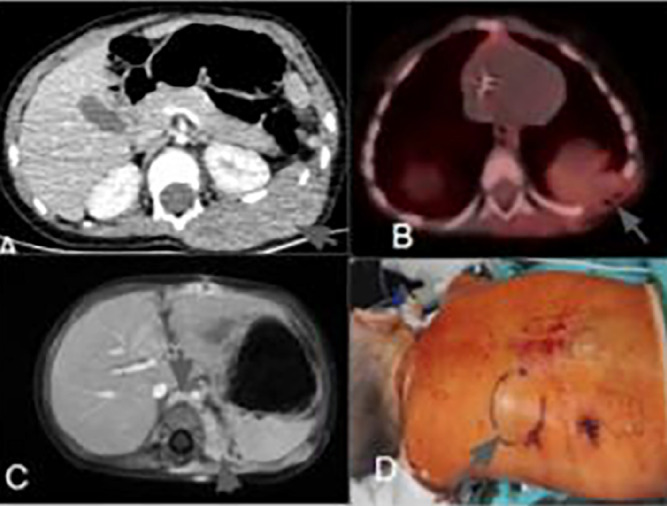

Abstract Image